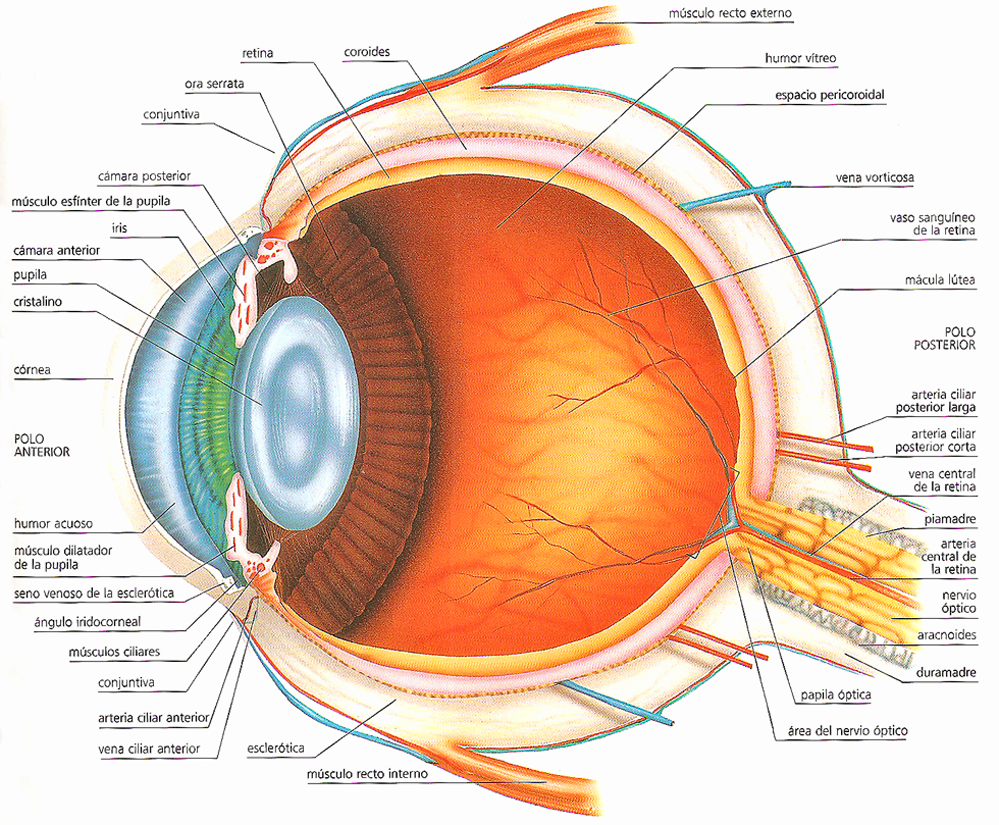

КТ-графики и изображение строения глаза